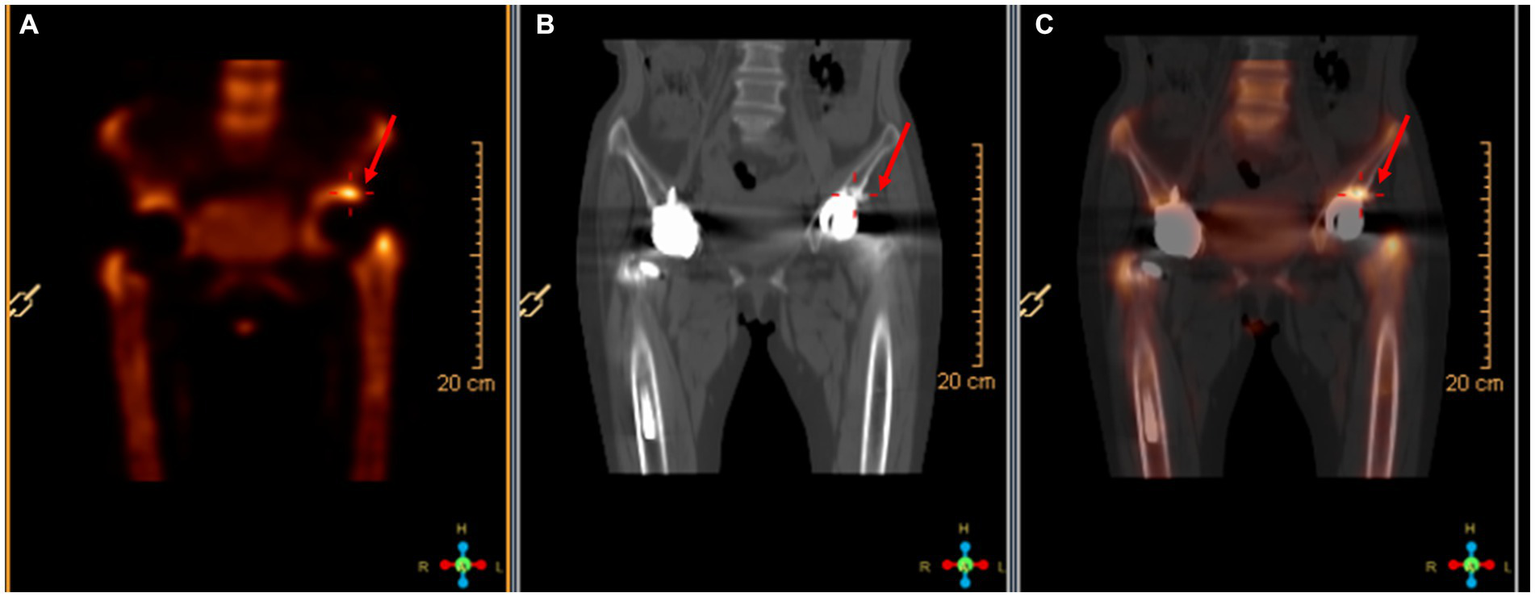

On April 13, a sample of pus from the fistula was collected for aerobic and anaerobic bacteria culture. Gram stain of the specimen revealed a moderate number of leukocytes but no organisms were seen. After 2 days of incubation, scanty growth of coagulase-negative Staphylococcus and Listeria monocytogenes were identified. Additional pus was collected 4 days later, with pure growth of Listeria monocytogenes isolates. Two sets of blood cultures were taken with incubation for 14 days, and additional stool specimens were sent with enrichment using blood agar with aztreonam, but these results were unremarkable. On April 22, whole-body bone scintigraphy (Technetium 99 m-methyl diphosphonate) showed an increased bone metabolism around the stem of the left femoral prosthesis and an increased radionuclide uptake in the blood pool phase, suggesting postoperative chronic infectious lesions (Figure 2). On April 24, magnetic resonance imaging (MRI) of the left hip joint showed inflammatory exudation around the upper end of the femur and surrounding soft tissue, and a subcutaneous abscess with fistula formation in the upper thigh (Figure 3). Transthoracic echocardiography and cranial MRI were performed, but no significant abnormalities were found. Upon further history taking with a food questionnaire, the patient reported consumption of pasteurized milk stored in the refrigerator, and she developed mild gastroenteritis approximately 1 month before infection. It is suspected that the patient may have consumed dairy products contaminated with L. monocytogenes, which entered the bloodstream via the gastrointestinal tract and then spread to the hip joint. Therefore, the patient was diagnosed with listeriosis presenting as a late-onset prosthetic left hip infection.

Figure 2

Radionuclide bone imaging. (A) The bone metabolism around the left femoral stem was increased. (B) The blood flow phase was normal. (C) The radioactive uptake in the blood pool phase was increased.